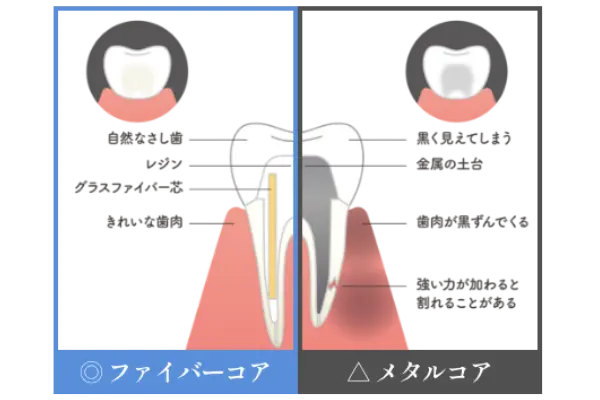

神経のない歯には、金属を使用しない「ファイバーコア」で

金属アレルギーや歯ぐきの変色を予防し、長持ちする土台を

「ファイバーコア」です

通常は神経のない歯にいれるコア(土台) はハイブリッドと金属の芯を用いてメタルコア(土台)で作られます。ただこのメタルコアは金属のため錆びてしまったり、溶け出した成分で歯や歯ぐきが変色することがあります。

また最大の問題は、歯と金属の柔軟性や堅さが異なることで「くさび」の様に作用して、根管治療をした大切な歯を割ってしまう歯根破折のリスクが高い点です。

当院ではこのコア(土台) の素材として「ファイバーコア」を推奨しております。金属を全く使用しないい素材であるファイバーコアは弾性(しなやかさ)があり、衝撃を吸収する特性もあるため歯を割ってしまうリスクを低減します。

白色で光を透過するので、被せ物の白い歯も自然な透明感となります。金属を一切使用しないファイバーコアは金属アレルギーの心配もありません。このようにファイバーコアは歯とからだに優しい歯科治療の土台となる素材です。